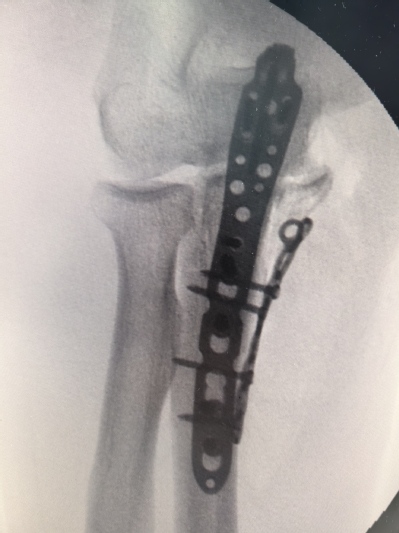

一名69岁男性,因不慎撞伤导致肘关节明显肿胀疼痛,不能活动,当即来苏州九院就诊。行x线检查后示尺骨近段粉碎性骨折。经过吴卫东、黄晟医生仔细读片后诊断为经尺骨鹰嘴孟氏骨折。骨折断裂情况严重,尺骨鹰嘴、尺骨冠突骨块分离,同时存在肘关节内侧不稳定,病情复杂,手术难度非常大。

此次手术,借助先进3D打印技术,精确复制了患者骨折部位的骨骼结构,为手术提供了直观、详尽的参考。经过吴卫东、黄晟手术团队的努力,患者的粉碎性骨折得到了有效治疗,术后恢复良好。